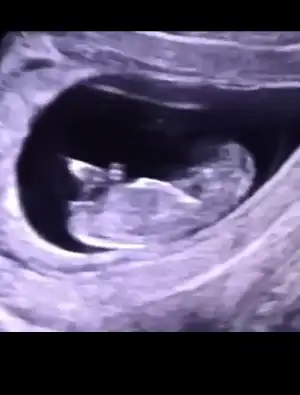

dr soylemeden siz gorun genital nub teorisi ( bebegin cinsiyeti)

bunada bakabilirmisiniz 11 haftalık

o kadar fazla araştırdım ki bu nub olayını beynim yandı benimde..

ama sizin usg çok net belli.. tabi bendeki tahmin sadece.. 😄

kız diyorum bu nub için..

hatta çizimi şöyle..